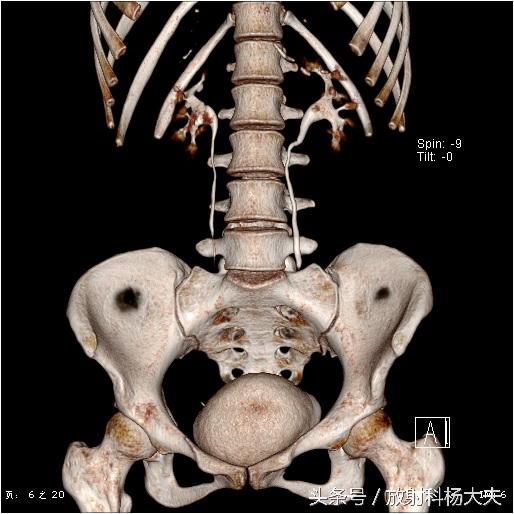

女孩的肾功能是好的,可以看到VR图像里双肾盂和输尿管显影很清楚。